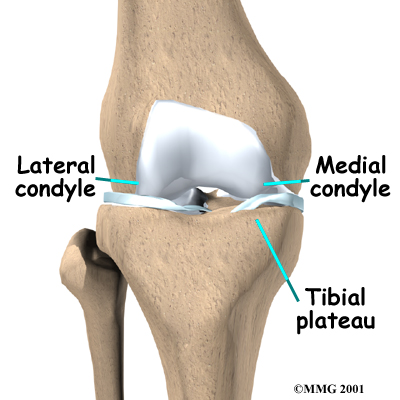

The knee joint is formed where the thighbone (femur) meets the shinbone (tibia). Two bony knobs on the end of the femur, called condyles, sit on the top surface of the tibia. The inside condyle (the one closest to the other knee) is called the medial femoral condyle. The lateral femoral condyle is on the outer half of the femur (farthest from the other knee). The top of the tibia bone forms a flat surface called the tibial plateau.

The knee is divided into two halves, or compartments. The medial compartment is the inside half of the knee and is formed by the connection of the medial femoral condyle and the tibial plateau. The lateral compartment is the outside half of the knee and is formed by the connection of the lateral femoral condyle and the tibial plateau.

covers the ends of bones. It has a smooth, slippery surface that allows the bones of the knee joint to slide over each other without rubbing. This slick surface is designed to minimize pressure and friction as you move.